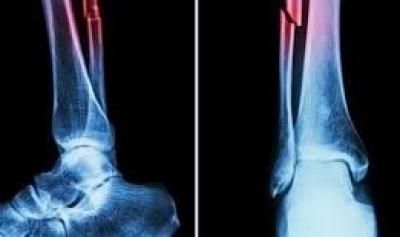

أعلن فريق بحثي في مقاطعة تشيجيانغ شرق الصين عن ابتكار طبي جديد يتمثل في "غراء عظمي" قادر على معالجة الكسور وتركيب الشظايا العظمية خلال ثلاث دقائق فقط في خطوة وُصفت بأنها اختراق علمي في عالم جراحة العظام.

ويتميز هذا الغراء بقدرته على التثبيت السريع والدقيق حتى في بيئة غنية بالدم، إلى جانب كونه يُمتص طبيعيًا من الجسم أثناء عملية الالتئام، ما يلغي الحاجة إلى عمليات جراحية لاحقة لإزالة المسامير أو الصفائح المعدنية.

وأكدت الاختبارات المعملية أن Bone-02 نجح في تحقيق نتائج جيدة من حيث السلامة والفعالية، حيث أُجريت إحدى العمليات في أقل من 180 ثانية، مقارنة بالوقت الطويل الذي تتطلبه الطرق التقليدية لزرع الصفائح والمسامير.